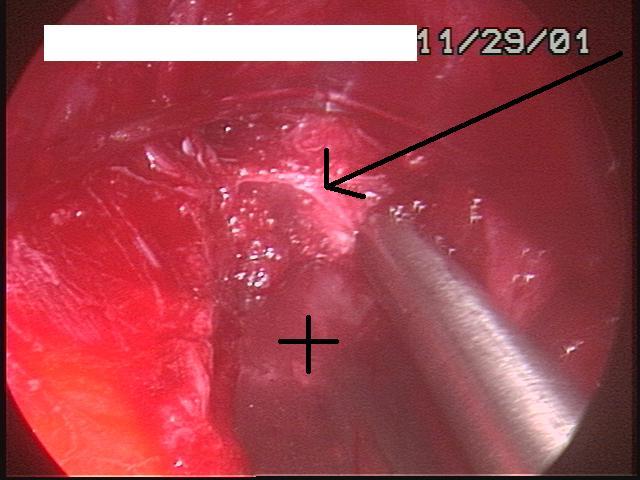

Once the tunnel reaches the sternum, the endoscopic tunneling device is utilized to visualize the clamp entering the interspace of maximal pectus depth and passing retrosternal (Figure 7). At the level of the sternum, these tunnels go retrosternal and communicate with each other. Ideally, even after entering the interspace, the tunnel stays extrapleural. The endoscopic view of the tunnel allows visualization of the safe passage of the clamp under the sternum and anterior to the pericardium. The mediastinum and pericardium can be seen pulsating posterior to the clamp. Two monitoring screens are utilized in order to allow excellent visualization by both the surgeon and assistant (Figure 8). Eventually, the larger curved clamp is easily passed under the sternum (Figure 9). This clamp is thus passed through one midaxillary skin incision and out the other midaxillary skin incision.

The clamp is then opened and used to grasp an umbilical tape and pull the tape through the tunnel (Figure 10). This umbilical tape is tied to two more umbilical tapes so that one tape can be used to pull a flat mediastinal tube through the tunnel and the second umbilical tape can act as a back-up. One umbilical tape is tied to a flat mediastinal tube. Then, this flat mediastinal tube is lubricated (Figure 11) and pulled through the tunnel and used to gently dilate the tunnel. The tunnel pathway is then endoscopically inspected to confirm hemostasis and satisfactory position of the flat mediastinal tube (Figure 12 ).

The bilateral ends of the bar are now tucked into the previously created pockets under a flap of muscle. Endoscopic inspection of the tunnel allows visualization of the tunnel, confirms adequate tunnel hemostasis, and documents excellent retrosternal bar position. The bar can be seen just posterior to the sternum (Figure 14). For larger patients with larger defects, two bars may be used.